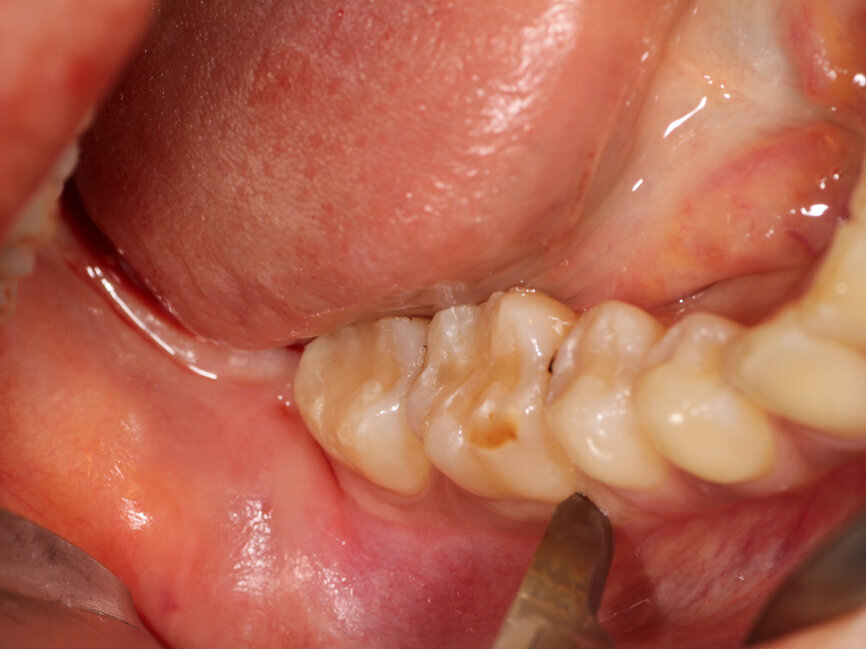

Fig. 5: A vertical releasing incision is made between the first molar and second premolar in the area to be flapped for donor site development in the right posterior mandible.

Next, the donor site would be addressed. A vertical releasing incision was created with a #15 scalpel blade between the right mandibular 1st molar and 2nd premolar (Fig. 5). A buccal sulcular incision was made on the first and second molars and continued as a crestal incision in the retomolar area buccal to the crestal midline, and a full thickness flap was elevated to expose the lateral aspect of the mandibular bone (Fig. 6). A mx-grafter (Maxilon, Hollis, N.H.) was utilized to scrape the exposed bone at the external oblique ridge to harvest autogenous bone to be incorporated into the graft to be placed in the maxillary anterior. The harvested bone was placed into a sterile dish (Fig. 7). Cortico-Cancellous 100-850 micron particle size, Particulate graft material (Osteolife Biomedical) was added to the sterile dish to increase the graft’s volume. The previously centrifuged blood taken at the beginning of the appointment, had the buffy coat portion (middle layer) drawn from the tubes and placed into the sterile dish with the harvested autogenous bone and particulate graft (Fig. 8). Following stirring the mixture, it was allowed to site for 10 to 15 minutes to allow completion of the clotting phase. The PRP buffy coat contains high levels of platelets, which will act as a glue to hold the graft into a flexible mass and prevent displacement during initial healing. Additionally, the plasma has high levels of platelet-derived growth factors (PDGF-AB), transforming growth factor (TGF-beta1) and cytokines that can affect inflammation, angiogenesis, stem cell migration and cell proliferation. The flap at the donor site was repositioned and closed with 4-0 interrupted PLA resorbable sutures (Violet, Osteolife Biomedical, Jupiter, Fla.) to achieve primary closure.